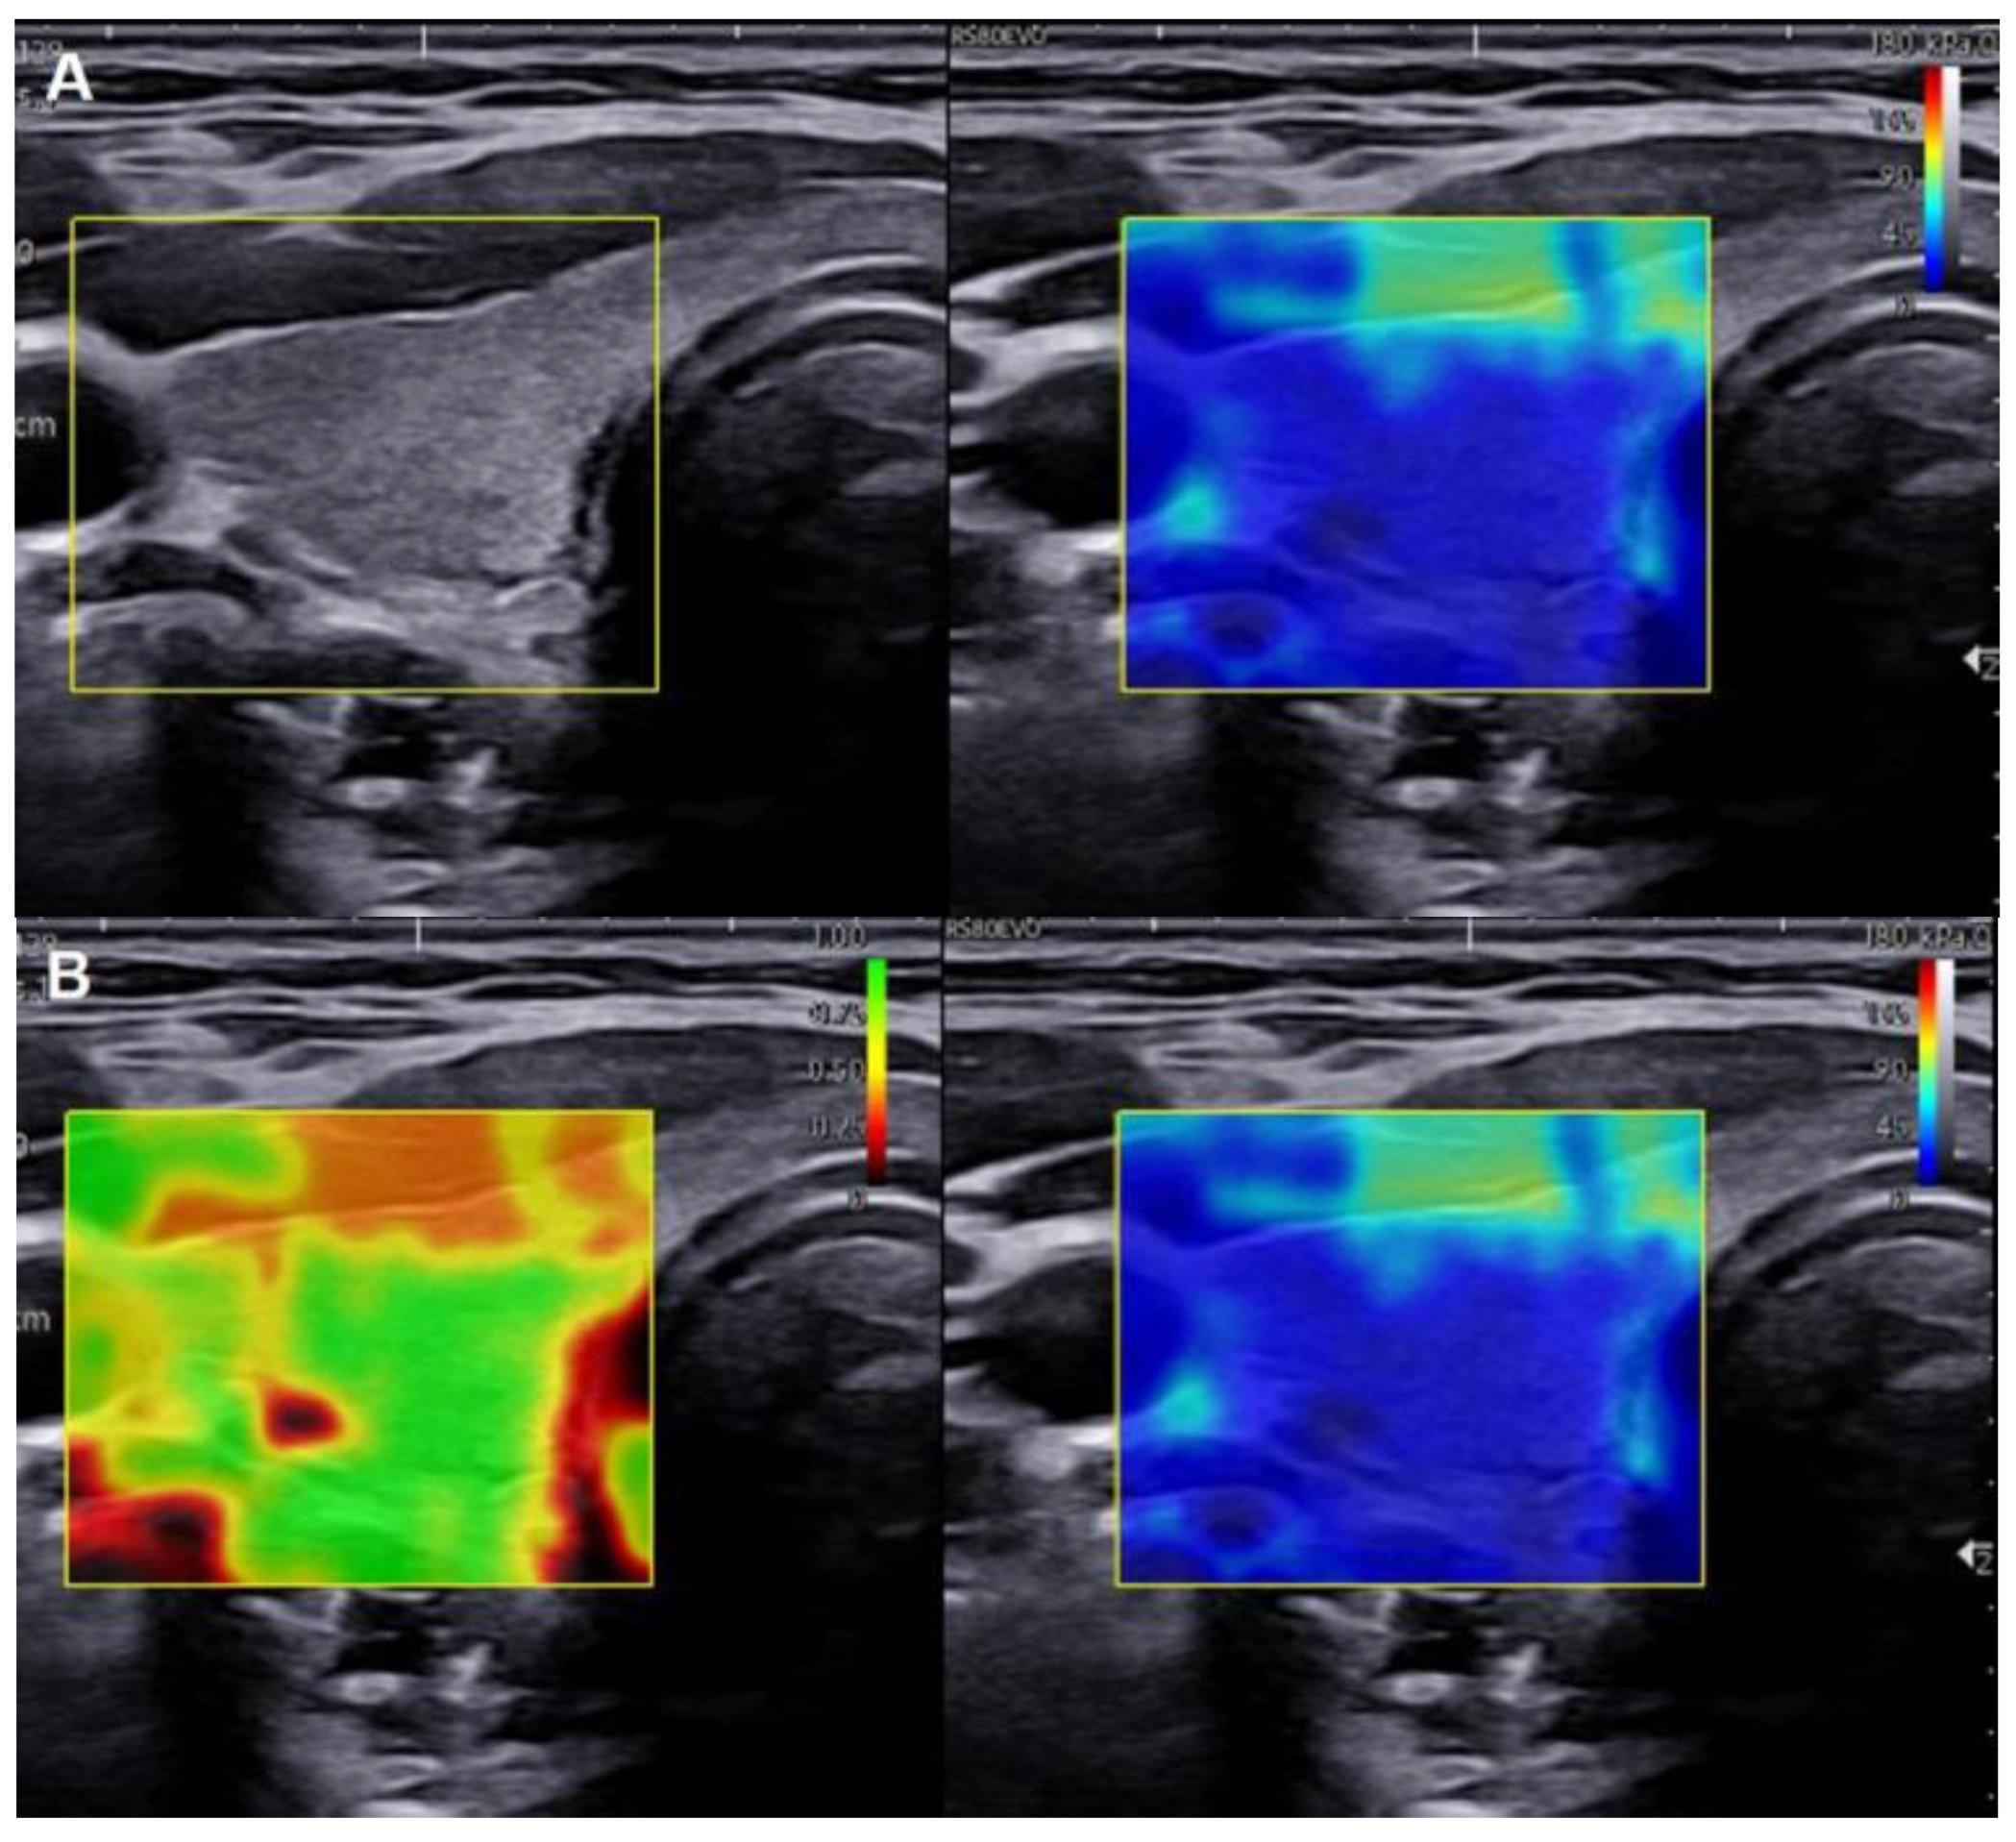

2.2. SWE Evaluation and Measurement